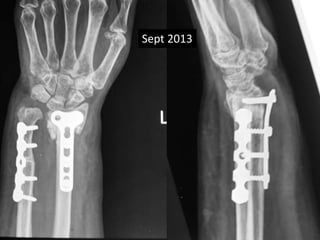

Surgery

• Volar exposure

• Removal of scar tissue and clearing of bone

ends.

• Release of soft tissue contractures.

• Shortening of ulna and plating.

• Plating of radius with bone grafting.

Feb 2013

April 2014

Sept 2013